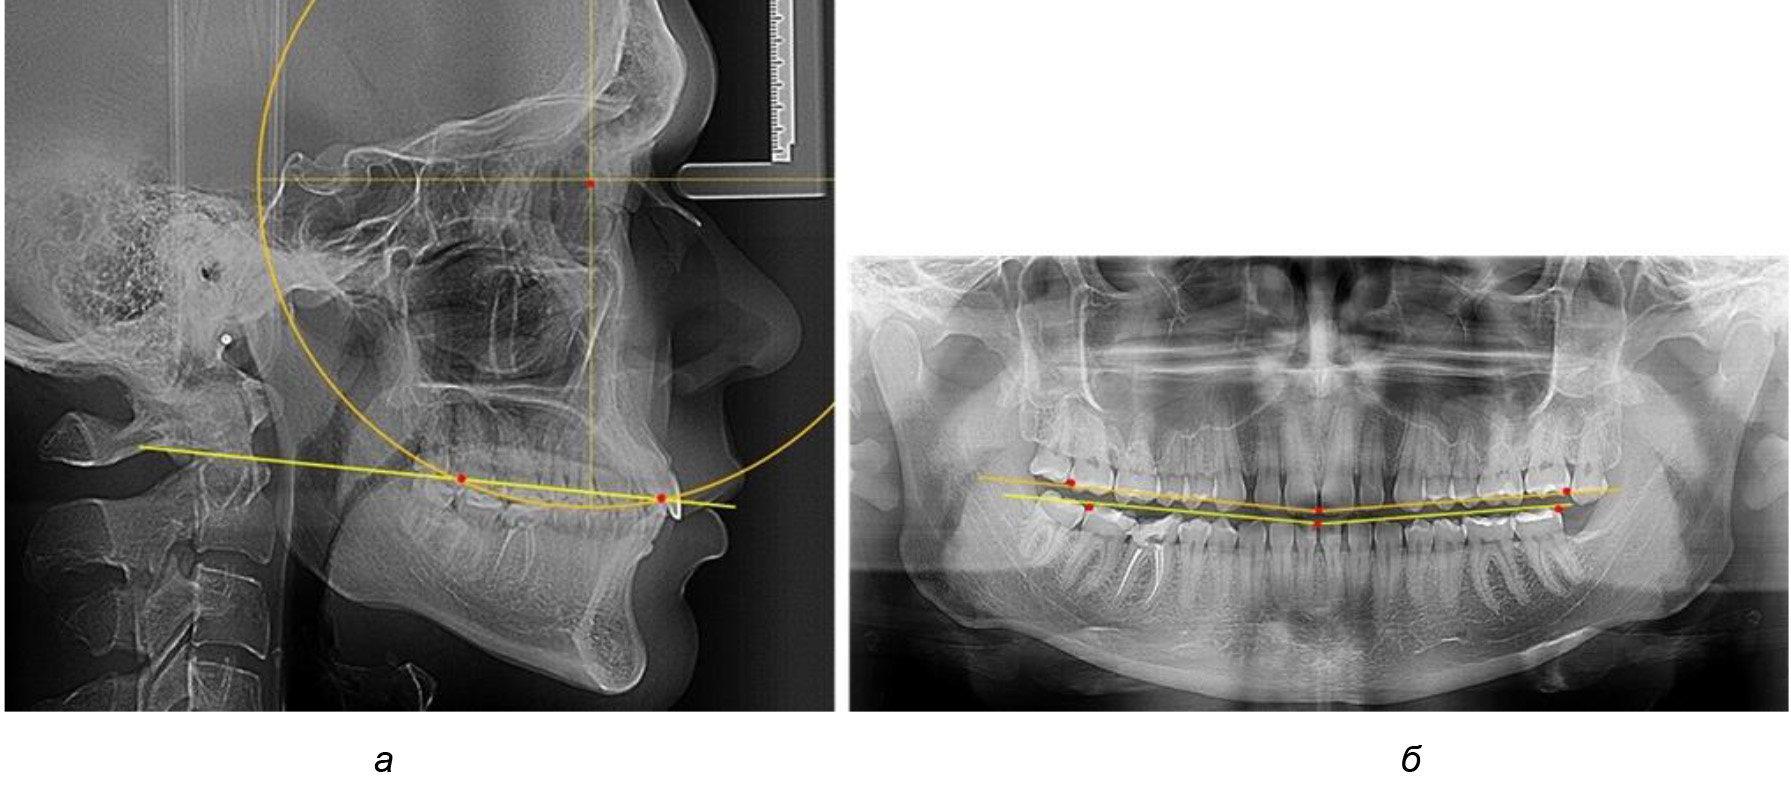

Глубина кривой Spee в среднем по 2-й подгруппе составила (5,69 ± 1,57) мм, что было достоверно больше, чем у людей с физиологической окклюзией (р ˂ 0,05). Достоверных различий с показателями, полученными при анализе ТРГ и ОПТГ, нами не отмечено (р ˃ 0,05). Отношение радиуса окружности к сагиттальному размеру окклюзионной линии в среднем по подгруппе составляло 1,372 ± 0,042 и не соответствовало числу Фибоначчи, что может быть использовано в качестве диагностического критерия определения патологической формы кривой Spee. После лечения пациентов техникой «прямой» дуги было отмечено незначительное увеличение сагиттального размера окклюзионной лини в среднем на (2,12 ± 0,77) мм. Однако окклюзионная линия практически касалась окклюзионного контура всех жевательных зубов, и отмечалось практически полное отсутствие кривой Spee.

Таким образом, проведенное лечение техникой «прямой» дуги способствует нормализации окклюзионного равновесия и торку передних зубов, однако не соответствует оптимальному окклюзионному статусу, характеризующему физиологическую окклюзию. При этом величина нижнечелюстного угла оставалась на прежнем уровне (рис. 5).

Рис. 5. Особенности ТРГ при патологической кривой Spee до лечения (а) и после лечения (б) техникой «прямой» дуги

После лечения пациентов техникой «прямой» дуги, так же как и в 1-й подгруппе, было отмечено увеличение сагиттального размера окклюзионной лини в среднем на (2,38 ± 0,83) мм. Окклюзионная линия практически касалась окклюзионного контура всех жевательных зубов, и отмечалось практически полное отсутствие кривой Spee, так же как и у людей 1-й подгруппы 2-й группы (рис. 6).

Рис. 6. Особенности ТРГ при оптимальной кривой Spee до лечения (а) и после лечения (б) техникой «прямой» дуги

Таким образом, проведенное лечение техникой «прямой» дуги способствует нормализации окклюзионного равновесия и торку передних зубов, однако не соответствует оптимальному окклюзионному статусу, характеризующему физиологическую окклюзию. При этом величина нижнечелюстного угла оставалась на прежнем уровне.